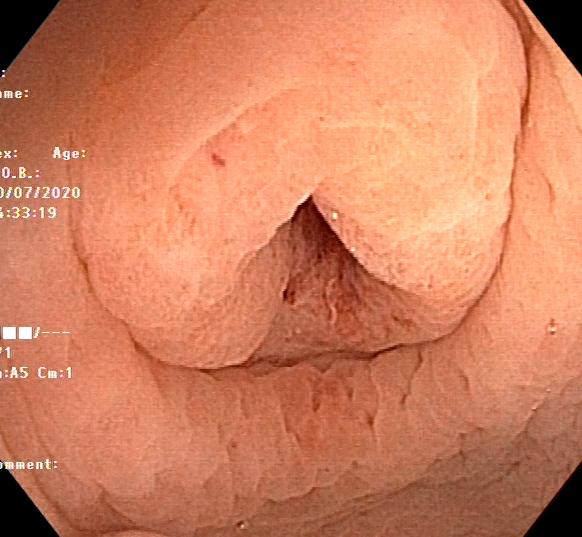

阑尾内口

然后下一步就阑尾口插管给它冲洗,冲出来很多的浓苔样的物质以及粪石,为了不影响大家心情,因此冲洗时候的视频就没有录制。

水下再观察一下干干净净的阑尾开口是不是很nice!